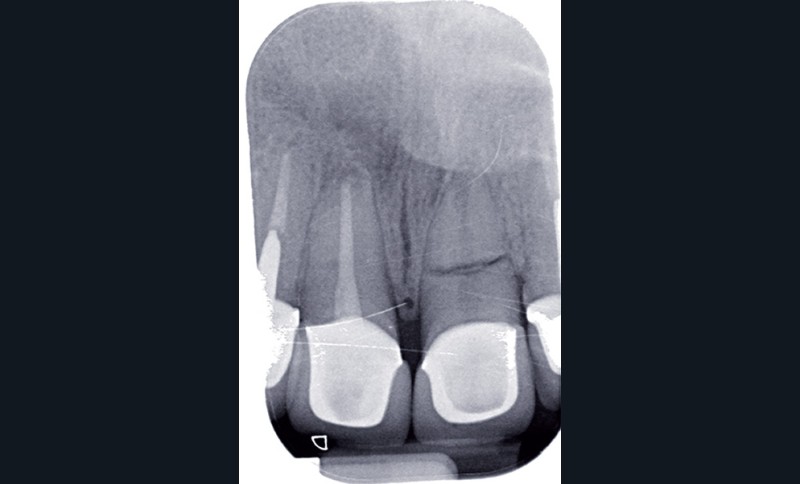

La réactivité clinique est la capacité d’un praticien à s’adapter et à envisager une solution thérapeutique. Cette séance, par son interactivité et par les différents cas cliniques exposés, va permettre aux praticiens de poursuivre leur enrichissement en situations cliniques. Ainsi, face à une fracture radiculaire (fig. 4a), la seule solution est-elle l’extraction ? Sur ce cliché (fig. 4b), la question est un peu provocatrice, et je vous engage à venir voir et écouter dans cette séance la solution apportée et surtout la pérennité de la décision choisie.